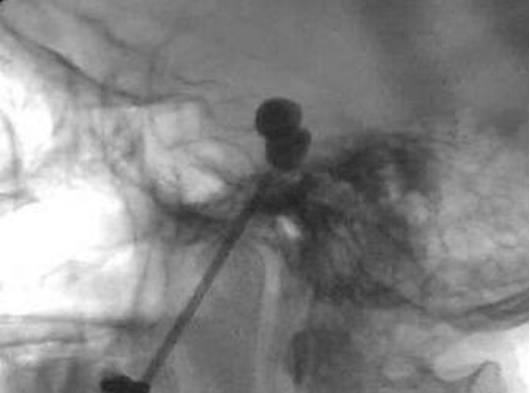

X线引导下,穿刺针进入卵圆孔后,准备4号Fogarty球囊导管,用造影剂检查球囊密封性是否完好并排除囊内空气。拔出穿刺针针芯,将球囊导管沿穿刺针管心插入,通过标记线可判断导管相对于针尖的进入深度,通常插入的导管比针尖深约17mm。由于球囊沿着Meckel’s腔上方充盈常导致其越过岩骨嵴而移位至后颅窝,故应尽可能地将球囊放在靠近颅底的位置。

最理想的球囊形状应为梨形外观。梨状球囊的囊内压力约为1000-1200mmHg,持续压迫约60-180s。通常不必测囊内压,可通过注射器注入造影剂时阻力变化来大致判断囊内压(0.75-1ml)。一旦阻力大到无法继续注射就应停止,强行注射会导致球囊爆裂。对再次手术患者,球囊压迫时间为120-180s。